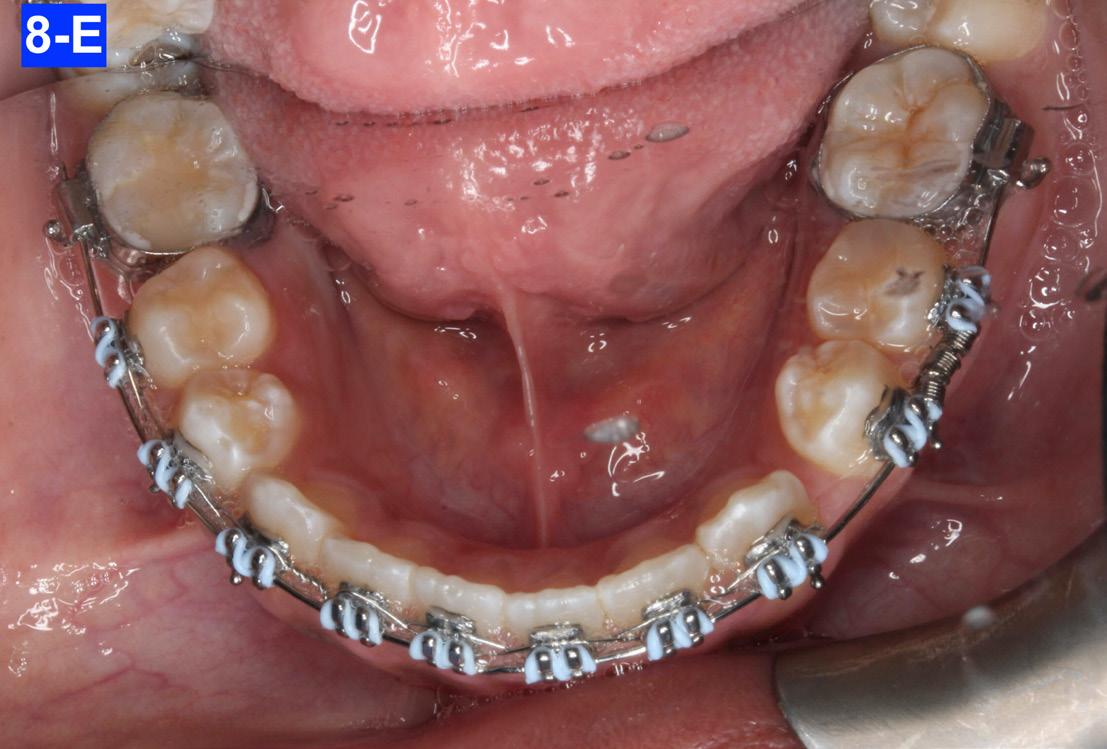

The maxillary and mandibular six anterior teeth were undertied with a lace-back (a .010 ligature tie) to crystalize the space closure. There was an open coil spring between #44(28) and #45(29) to close the space between the first bicuspid and the cuspid. In addition, there were ¼ " , 4.5 oz triangular elastics stretched between the maxillary cuspids and mandibular cuspids and bicuspids (8-A, B, C, D, E).

Fig. 8-E: Mandible, occlusal view